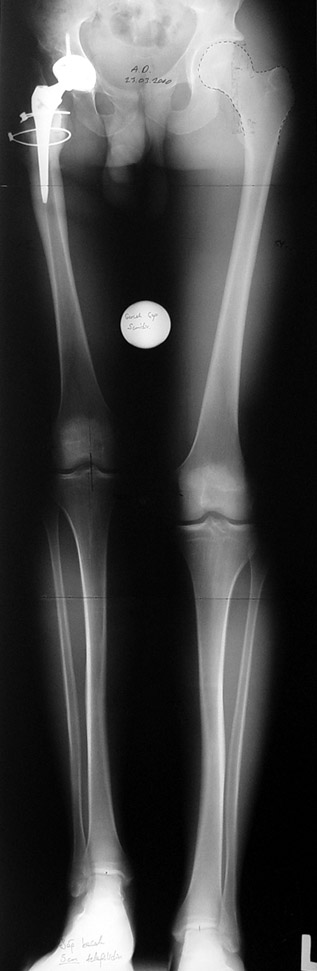

Case 1